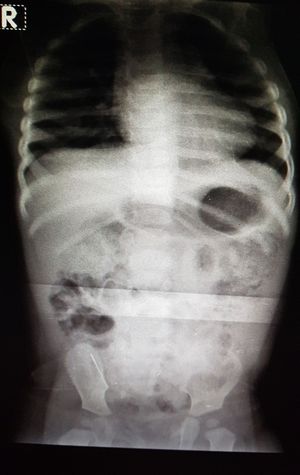

Foreign body ingestion by 11 month baby

Guess where and what is the foreign body

A straight pin?? On lower left of xray, patient's lower right??

Your right Mark.:)

A pin